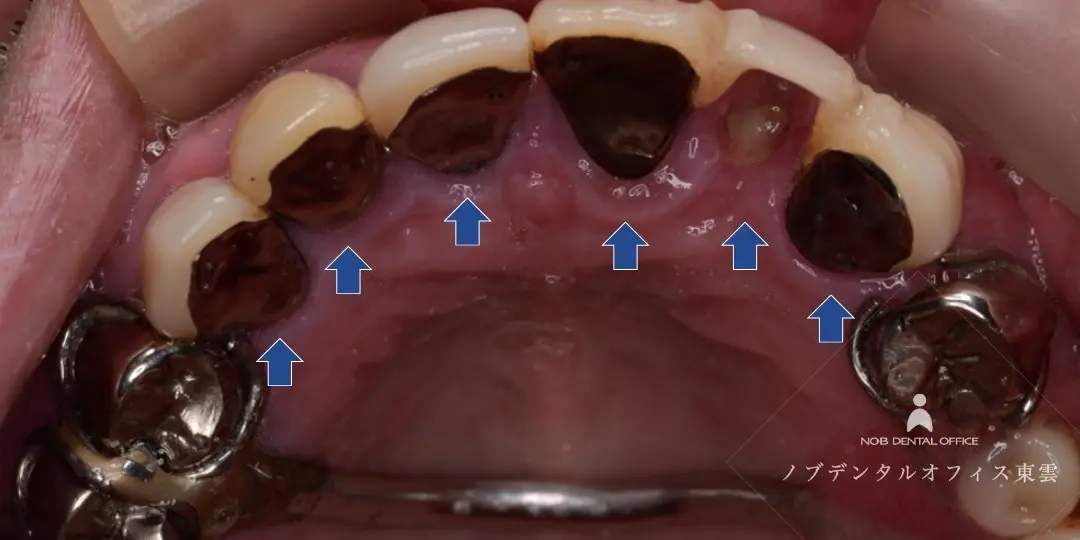

前歯をブリッジで治療した症例(40代女性)

上の前歯2本を失い、仮歯が入っている状態でした。

インプラント・ブリッジ・入れ歯の治療計画をお話しさせていただき、治療期間やリスク、強度や審美性を踏まえて、ブリッジ治療を行いました。

両隣の歯はいずれも神経がなく歯質が薄い状態でした。歯の根のトラブルが起きるとブリッジを取り外すことになってしまうので、補強もかねて根管治療の再治療を行ない、ブリッジの支台歯にしました。

セラミック完成前に仮歯に置き換え、見た目・発音・噛み合わせを調整した上で、セラミックのブリッジを作製しました。

前歯の目立つ場所でしたが、ジルコニアのブリッジで自然な仕上がりになっています。